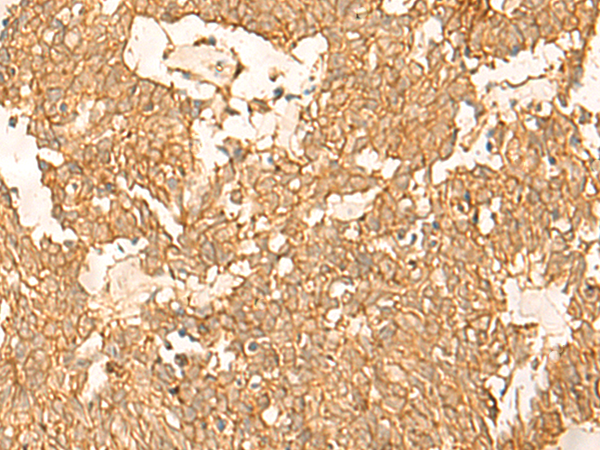

分类: 科研抗体货号: P04140别名: BCL8B, LYST2应用: IHC反应种属: Human, Mouse